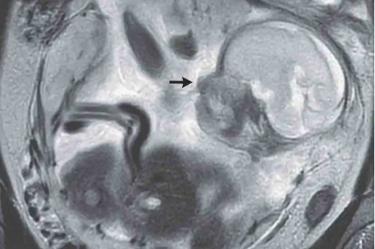

En una rara anomalía médica, una mujer se sorprendió al saber que estaba embarazada de 23 semanas y que el bebé crecía dentro de su intestino.

Sin embargo, se trataba de un embarazo ectópico abdominal, en el que el óvulo fecundado se implanta fuera del útero y en su lugar en la cavidad abdominal, y que sólo representa aproximadamente el 1 por ciento de los embarazos ectópicos.

Los embarazos ectópicos, que representan menos del 2 por ciento de todos los embarazos y suelen producirse en las trompas de Falopio, son peligrosos para la madre, ya que pueden causar hemorragias internas, rotura de trompas o shock, y rara vez sobreviven los fetos.